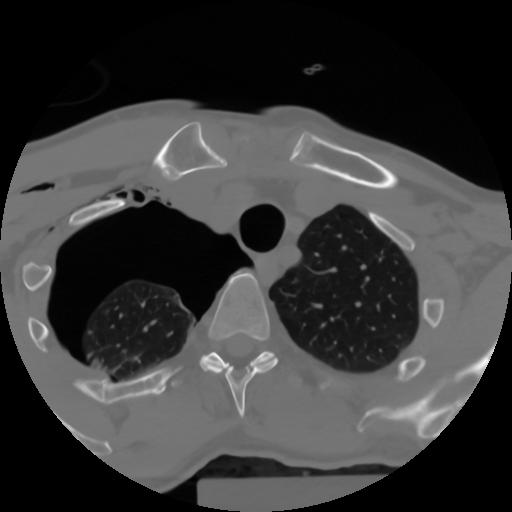

10 P.BLANDAS,,Axial,2.0,P.BLANDAS,,